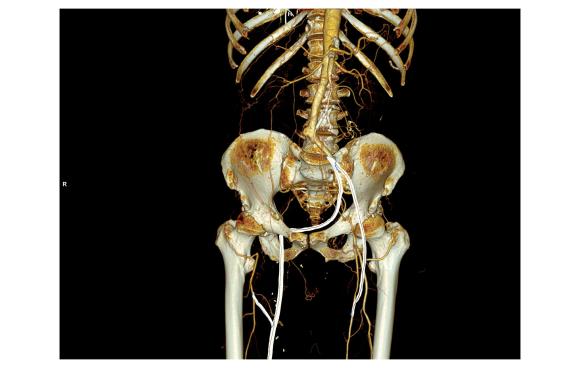

On examination, he had heavy scarring in both groins from prior open incisions healed by secondary intention, a midline laparotomy incision. He had weak bilateral axillary and brachial artery pulses. He had no pulses in either leg. The right foot had gangrene of the distal phalanx of the third toe. The both feet were anemic and painful -the left foot had more dependent rubor. Pulse volume recordings were flat in both legs. TCPO2 was in the 20-40mmHg range at the thighs bilaterally suggesting reduced potential for healing an above knee amputation. Vein mapping showed no suitable saphenous vein in either leg. CTA (figure below) showed both external iliac arteries to be occluded or absent and the common femoral arteries to be occluded or missing bilaterally.

The left femoral bifurcation was preserved and the left SFA was patent into small underfilled tibial vessels. On the right, there was an isolated segment of profunda femoral artery that reconstituted from pelvic collaterals. The right below knee popliteal artery reconstituted and had underfilled but patent three vessel runoff (figure below).